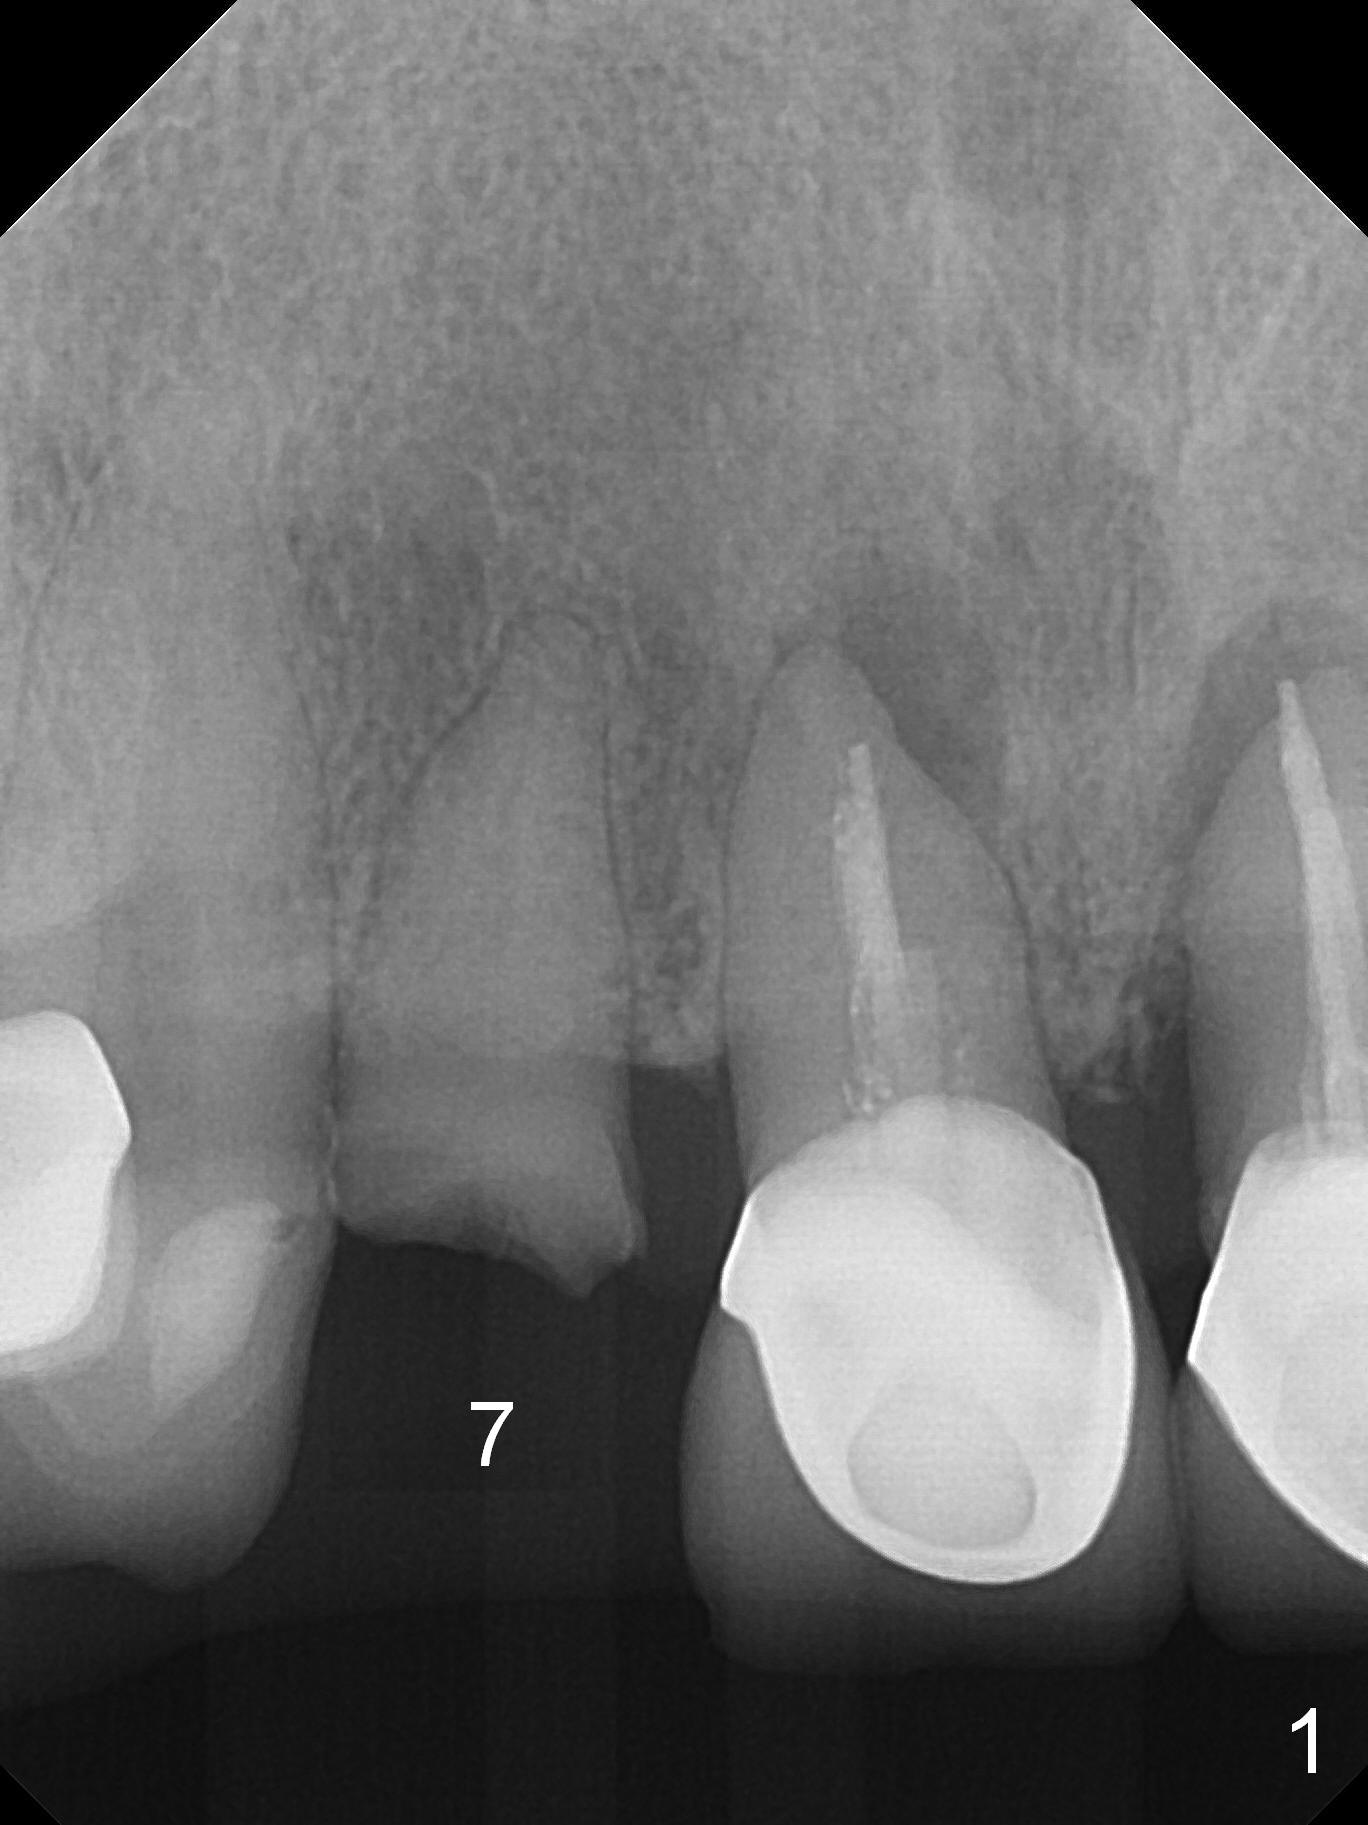

A 60-year-old woman has multiple restoration and no lower posterior teeth (replaced with RPD). The tooth #7 fractures (Fig.1). When an immediate implant is placed (Fig.2, no Antibiotic) with immediate provisional (using the existing crown), occlusal clearance is critical. Check overbite often and take photos. If the root seems to be ankylosed, socket shield will be performed.

In fact the residual root (Fig.3) is easy to remove. A 3.8x16 mm implant is placed (Fig.4 (with 2 mm buccal gap)) at the level as planned (Fig.2). Insertion torque is acceptable. After placing a 4.5x5(3) mm gold-coated abutment and allograft (Fig.5), an immediate provisional is fabricated (the existing crown is lost). The patient is pleased with the quick, painless procedure.